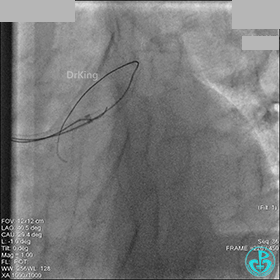

先处理前降支开口严重狭窄并顺利植入前降支到左主干支架。

没有说明是否进行了右冠脉介入治疗。